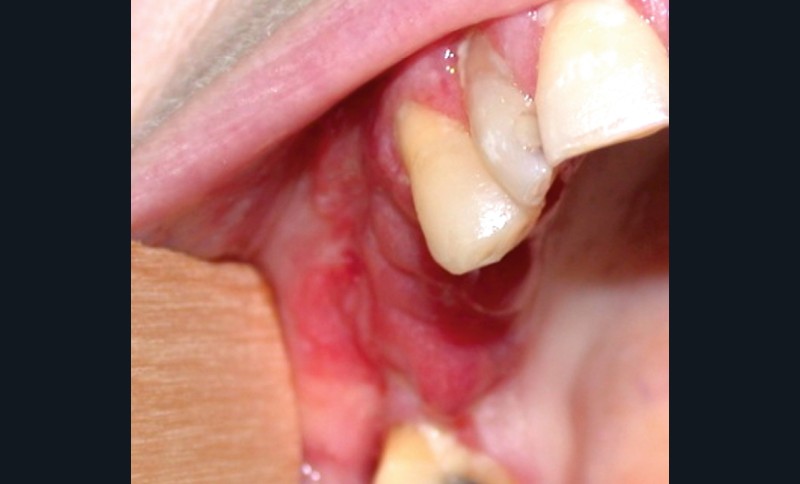

Érythroplasie isolée : elle se caractérise par une macule (fig. 2a), une plage (fig. 2b), une plaque (fig. 2c) limitée sans cause évidente.